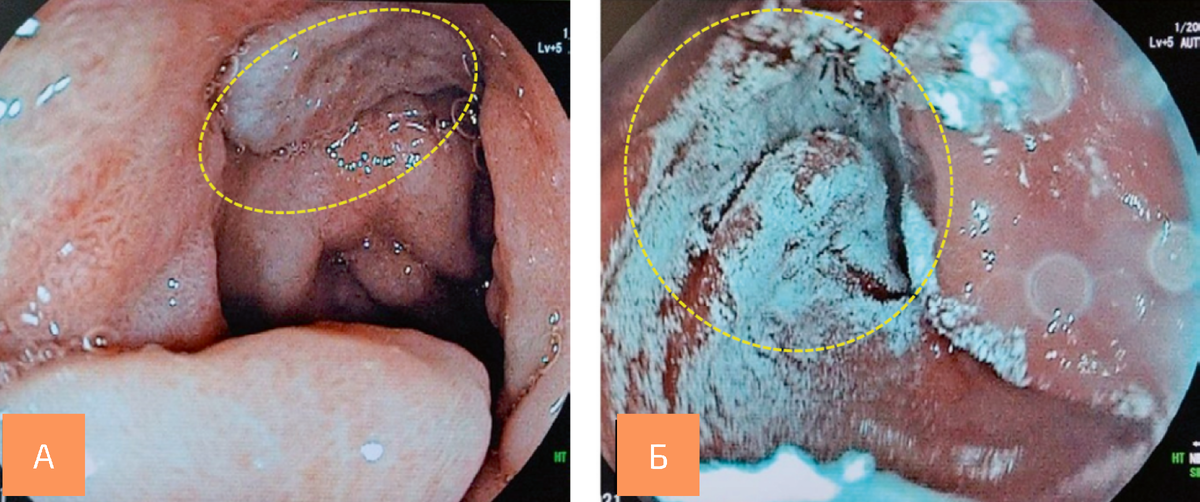

A — язвенный дефект передневерхней полуокружности луковицы двенадцатиперстной кишки (отмечено фигурой); Б — нанесение альгинатного полимерного полисахаридного гемостатического гидрогеля на язвенный дефект (отмечено фигурой)

В рамках лечебной диагностической процедуры на поверхность язвенного дефекта наносили порошкообразный альгинатный гемостатик. На поверхности язвенного дефекта формировался плотно фиксированный прозрачный гидрогель.